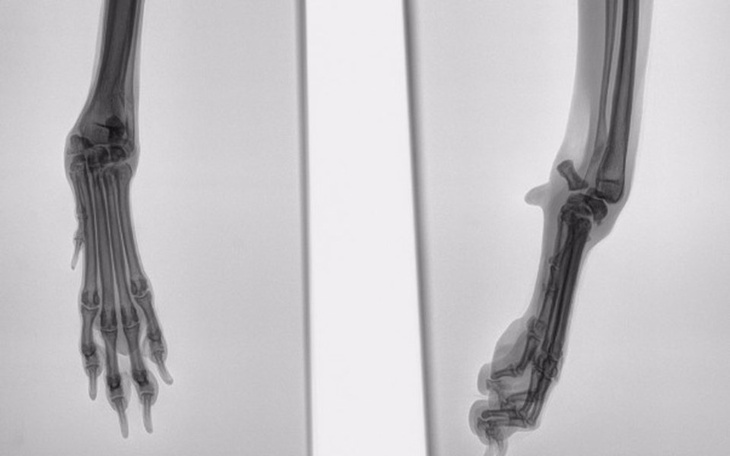

Od razu rzuciło nam się w oczy, że psiak ma nienaturalnie wykrzywioną łapę. Nawet się nie zastanawiając, ruszyliśmy do lecznicy! Tam okazało się, że Suchy nie ma czipa ani tatuażu. Mimo tego wierzyliśmy jeszcze, że znajdzie się jego właściciel, a cała sytuacja okaże się jakimś dziwnym wypadkiem...

W międzyczasie szukaliśmy również pomocy dla krzywej łapki. Niestety weterynarze rozkładali ręce... Wedle obrazu RTG można było jedynie podjąć decyzję o amputacji lub wspierać psiaka preparatami poprawiającymi pracę stawów.